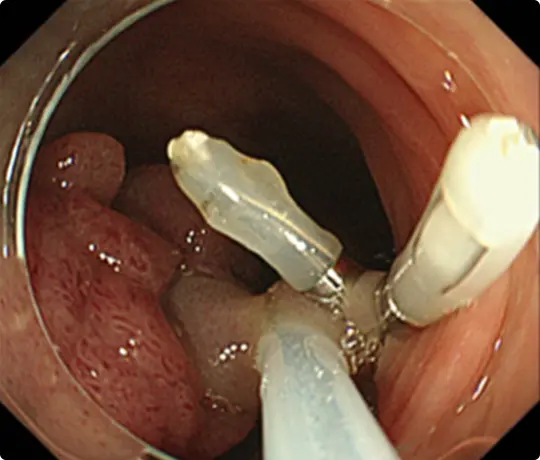

約3cmの大きな大腸ポリープです。

スネアでポリープの根元を縛り、電流を流して切除します(出血予防のためポリープの根元にクリップをうっています)。

切除した検体です。病理検査で早期大腸がんと診断されました。がんは完全に切除されており、治癒と判定されました。